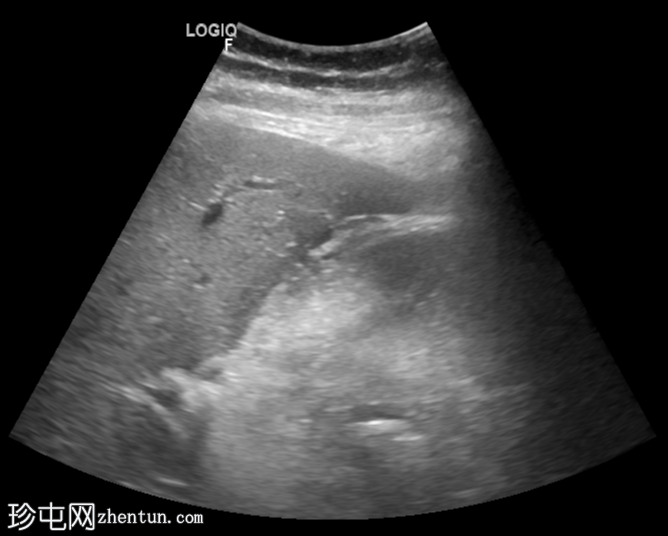

横切面

胆囊扩张,充满回声不均的异质性高回声物质(高回声、等回声、低回声),并可见漂浮回声。

可见胆囊周围水肿,胆囊壁不对称增厚,呈局灶性断裂,胆囊壁内可见强回声灶和强回声线(可能为气体腔)。

总体表现提示复杂性胆囊炎(坏疽性)。